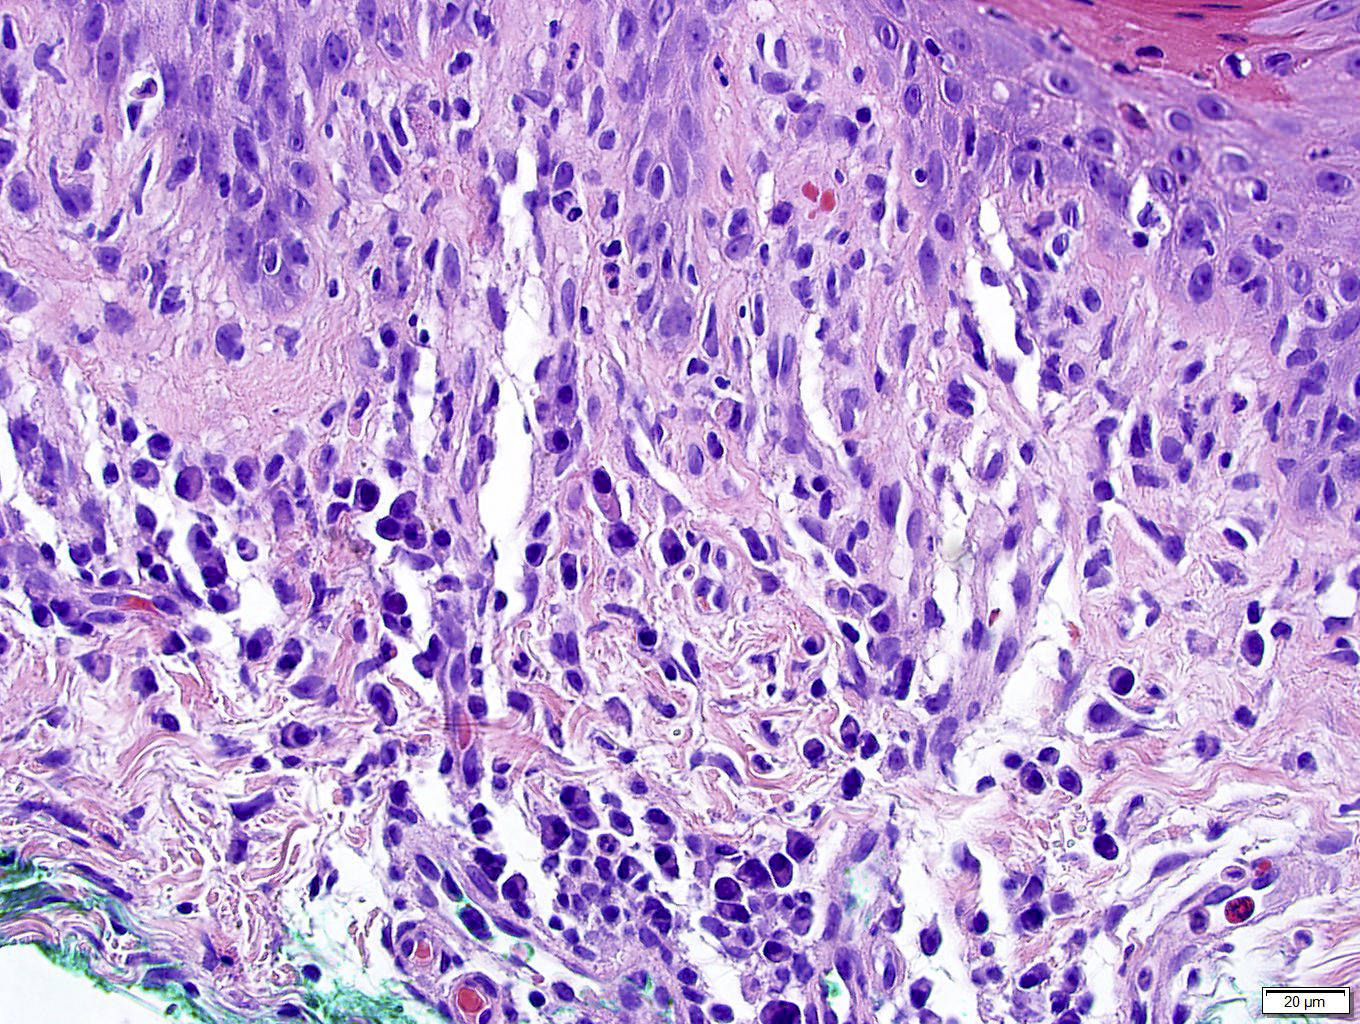

Microscopic (histologic) description

- Secondary syphilis:

- Lichenoid superficial and deep perivascular and periadnexal lymphohistiocytic inflammation with admixed plasma cells

- Plasma cells may be absent in 33% of biopsies

- Eosinophils can be present

- Marked endothelial swelling and proliferation of blood vessels can be seen

- Commonly identified are vacuolar interface change, acanthosis or lymphocyte exocytosis

- In late secondary syphilis, granulomatous inflammation may be present

Microscopic (histologic) images

Contributed by Silvija P. Gottesman, M.D., Hillary Rose Elwood, M.D., Mark R. Wick, M.D. and AFIP images